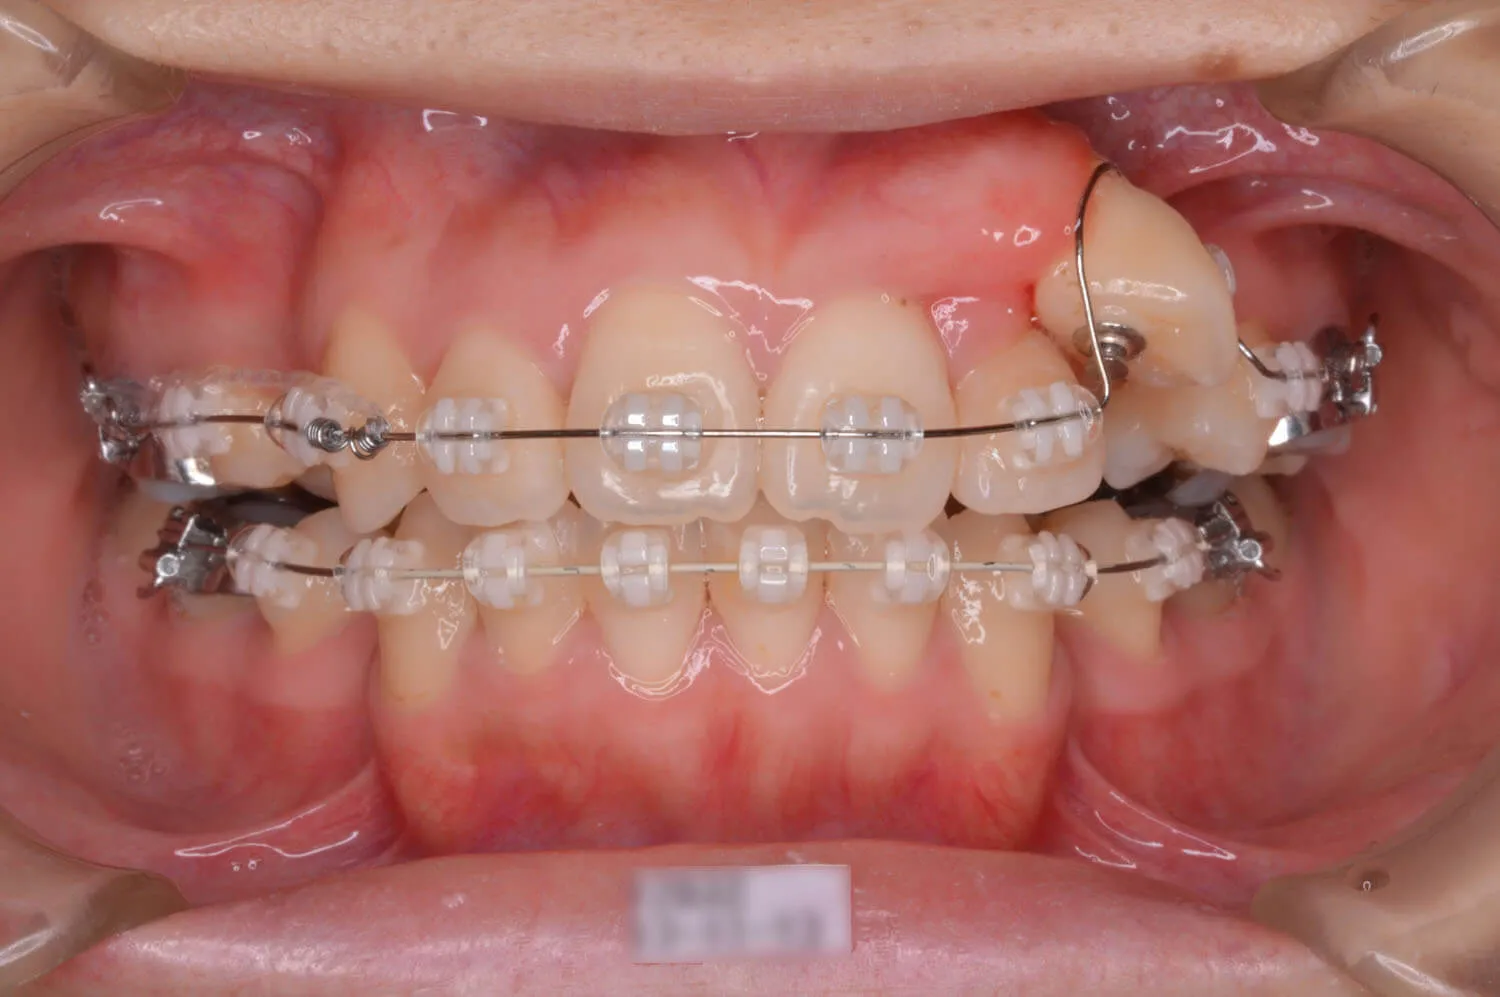

犬歯の位置が変わってきました。

犬歯が歯列に並んできました。